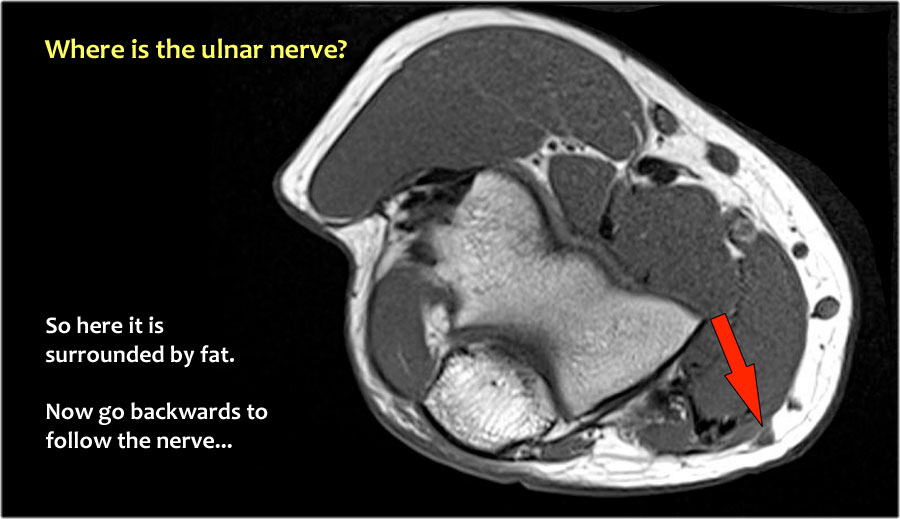

Một cách để thực hiện là đi theo các cấu trúc về phía xa cho đến khi tìm thấy dây thần kinh trụ ở phía xa tại vị trí bình thường của nó ở vùng cẳng tay gần được bao quanh bởi mô mỡ.

Sau đó khi bạn theo dõi nó về phía gần, bạn sẽ nhận thấy rằng đây là một trường hợp chuyển vị dưới da.